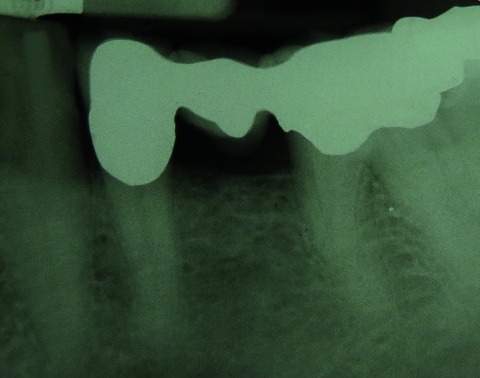

Fallbeispiel: Enchondrom

Zur Risikoklassifizierung von gutartigen Knochentumoren für die Beurteilung der allgemeinen Dienst- und Verwendungsfähigkeit von Soldaten Kevin Dallacker-Losensky¹, Magnus Scheer², Inken Seelmann¹, Michael Uhl³ ¹Sanitätsversorgungszentrum Volkach…